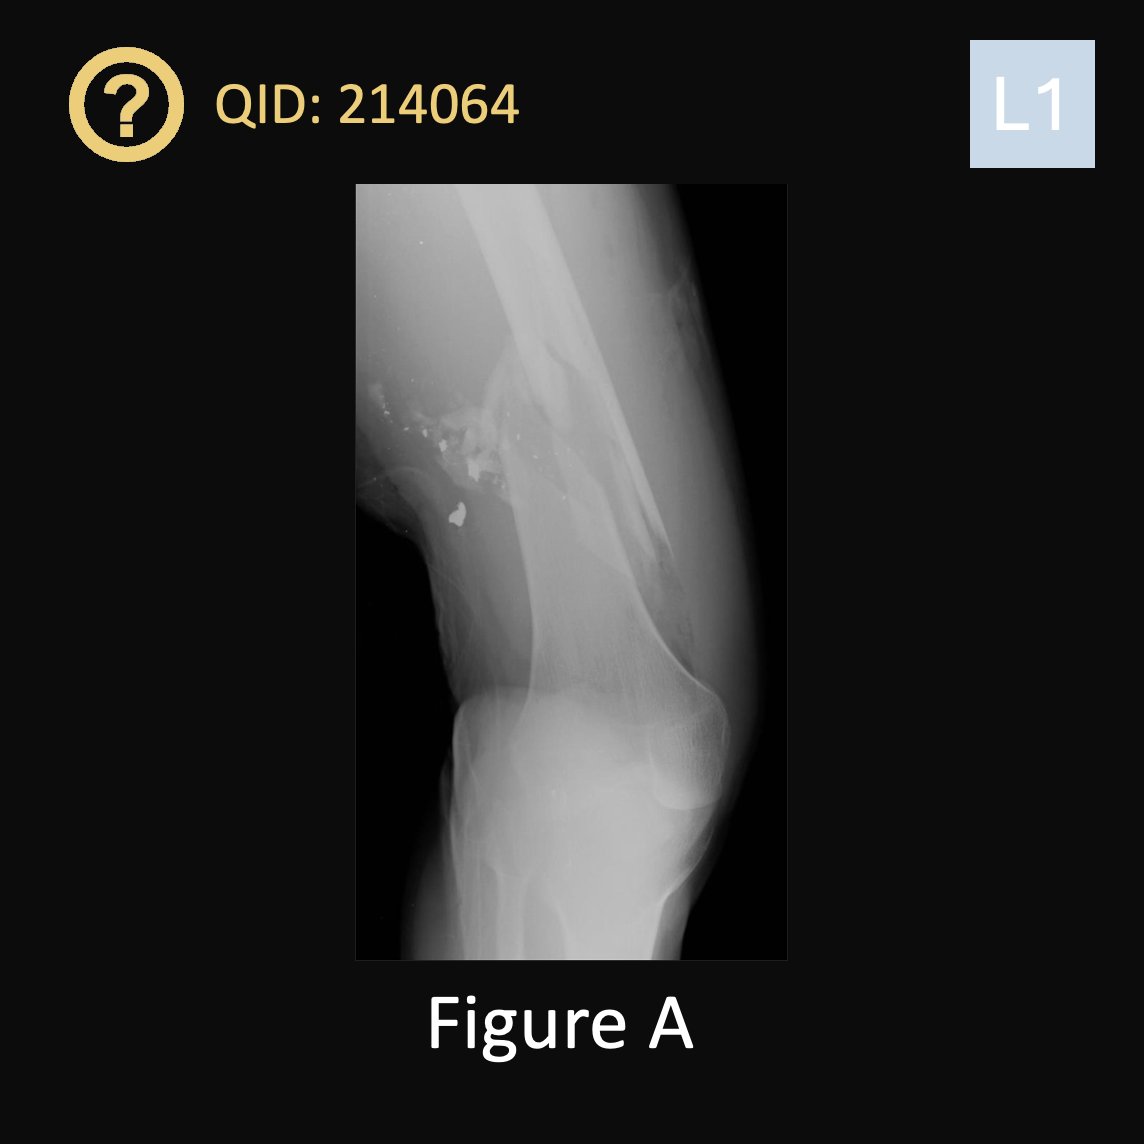

Figure A is the radiograph of a 45-year-old male who presents to the trauma bay following a gunshot wound. On examination, two wounds, one anteriorly and one posteriorly, are identified. You perform an ABI. Which of the following results would heighten your concern for associated vascular injury and cause you to order a CT angiography?

1. 0.81

2. 0.93

3. 1.01

4. 1.14

5. 1.28

QID: 214064

Comment your answer below, then check to see if you got it correct by clicking the link below to see the answer & explanation.

bit.ly/4dmu70X